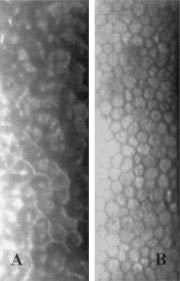

각막내피세포 검사 (specular microscopy)를 이용하여 비정상적인 부분을 촬영시

정상적인 각막내피세포보다 더 크고 어두우며, 한가운데 밝은 흰점이 있는 비정상적인 각막내피세포가 있습니다.

이러한 세포들은 세포의 한가운데에 밝은 점 혹은 세포벽 테두리를 따라서 밝은 선을 가지는 어두운 영역으로 관찰됩니다.

이러한 세포들은 ICE syndrome 에서 특징적인 양상이기 문에, ICE cell 이라고 합니다.

이를 Hammered Silver 라고하는데, ICE cell 을 현미경으로 관찰하였을때 특징적인 모양을

이렇게 표현합니다.